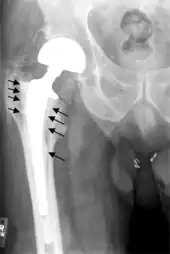

Hip prosthesis displaying aseptic loosening (arrows)

Hip prosthesis zones according to DeLee and Charnley,[29] and Gruen.[30] These are used to describe the location of for example areas of loosening.

On radiography, it is normal to see thin radiolucent areas of less than 2 mm around hip prosthesis components, or between a cement mantle and bone. These may indicate loosening of the prosthesis if they are new or changing, while areas greater than 2 mm may be harmless if they are stable.[31] The most important prognostic factors of cemented cups are absence of radiolucent lines in DeLee and Charnley zone I, as well as adequate cement mantle thickness.[32] In the first year after insertion of uncemented femoral stems, it is normal to have mild subsidence (less than 10 mm).[31] The direct anterior approach has been shown to itself be a risk factor for early femoral component loosening.[33][34][35]